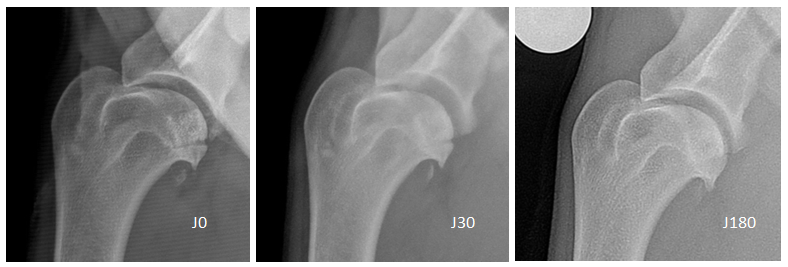

Contrôles radiographiques à J30, J90 et J180 après implantation d’un implant biphasique en céramique. La céramique est parfaitement biocompatible et elle s’intègre parfaitement dans l’os.